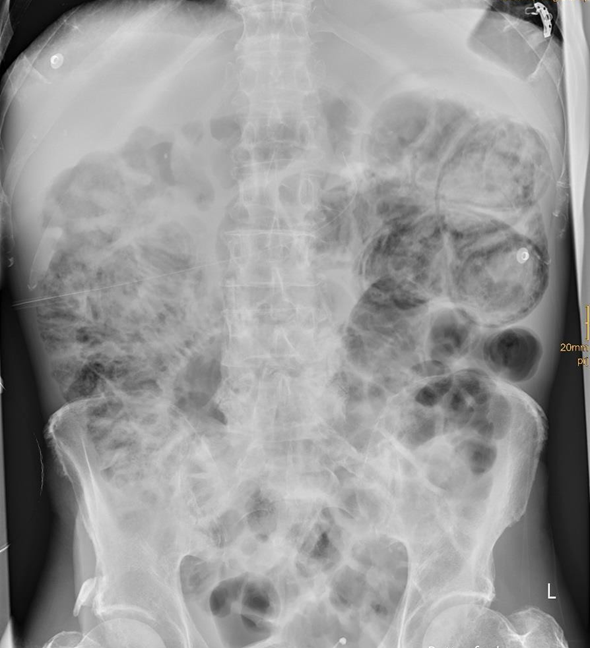

Gasansammlung in der Wand des Intestinums